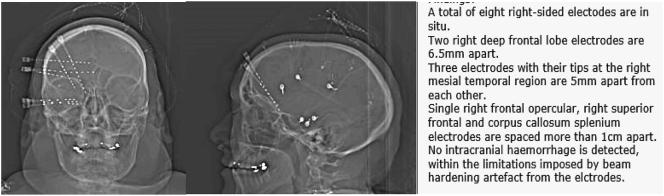

https://cdn.ncbi.nlm.nih.gov/pmc/blobs/fb37/6310735/50cc154cb328/gr1.jpg